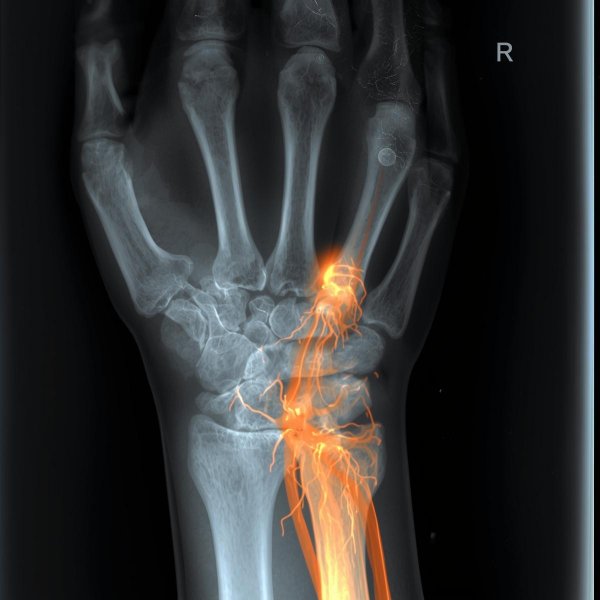

Le syndrome du canal carpien correspond à une compression du nerf médian au niveau du poignet, dans un “tunnel” étroit (le canal carpien). Cette compression provoque surtout des fourmillements / engourdissements et parfois des douleurs, souvent pire la nuit, et peut évoluer vers une faiblesse de la main si elle devient sévère.

Les signes typiques sont des fourmillements/engourdissements nocturnes dans le territoire du nerf médian (pouce–index–majeur) avec parfois douleur et maladresse. L'examen clinique et, si besoin, un ENMG aident à confirmer.